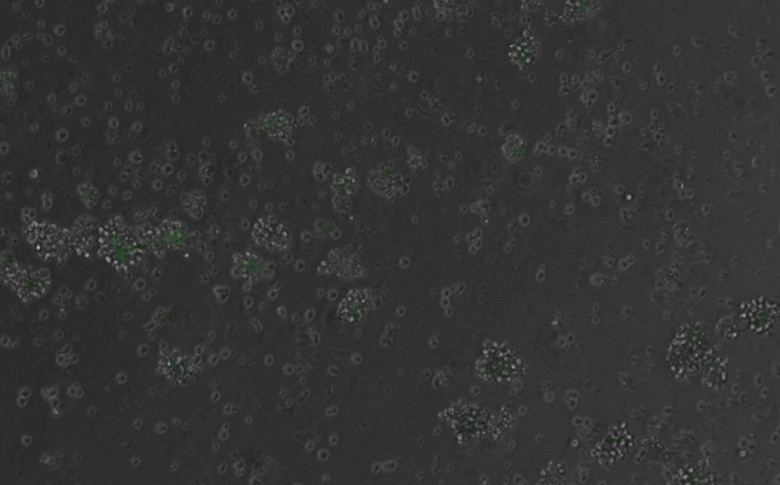

Искусственный интеллект взломал код жизни: созданная им ДНК впервые управляет генами в клетках млекопитающих

Ученые из Центра геномного регулирования в Испании совершили прорыв в биологии: искусственный интеллект создал молекулы ДНК, которые впервые успешно управляют генами в здоровых клетках млекопитающих. ИИ разработал искусственные фрагменты ДНК, которые могут включать или выключать гены в нужных клетках, например, заставлять стволовые клетки превращаться в клетки крови. Это как программирование для живых организмов.

Ученые синтезировали эти фрагменты химически и с помощью вируса доставили их в клетки крови мышей. В экспериментах ДНК интегрировалась в геном клеток в случайных местах. ИИ спроектировал энхансеры, которые активировали ген, кодирующий флуоресцентный белок, чтобы ученые могли видеть, работает ли система. Результаты были точными: гены включались в нужных клетках, не затрагивая другие.

Фото: CAina Bernal Martinez/Centro de Regulacion Genomica

Фото: CAina Bernal Martinez/Centro de Regulacion Genomica Доктор Роберт Фромель, первый автор исследования, сравнил процесс с написанием программ для биологии: «Это дает невероятную точность в управлении клетками». Технология может изменить лечение болезней, связанных с нарушением работы генов, таких как рак или аутоиммунные расстройства. ИИ позволяет создавать энхансеры, которых нет в природе, и настраивать их так, чтобы они работали только в определенных клетках, минимизируя побочные эффекты.